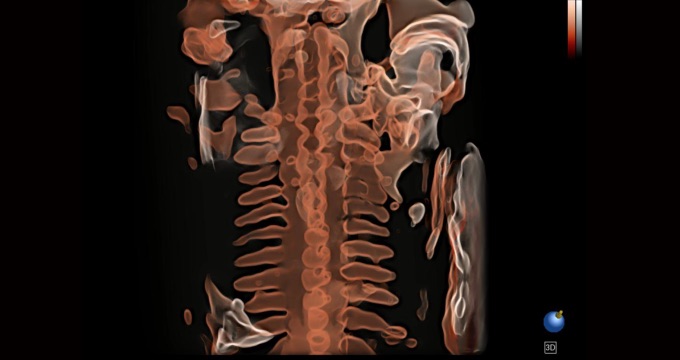

小器官应用

三维光影成像技术采用新型的渲染方式,增强边缘信息,使得轮显示清晰完整,为临床提供丰富、直观的三维结构,提供临床诊断准确性。